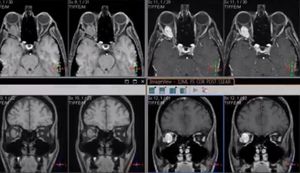

Fibrous mass of the right orbit

Fibrous mass of the right orbit: exhibiting the value of fat suppression in Orbits MRI, courtesy of MRIquiz.com